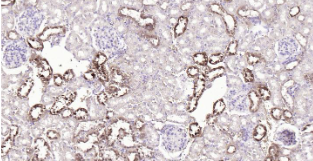

Immunohistochemical analysis of paraffin embedded mouse kidney tissue slide using IHC0215M (Mouse S100A1 IHC Kit).